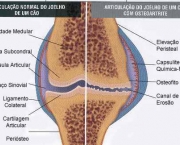

Também conhecida como gonartrose, a osteoartrose do joelho é uma enfermidade degenerativa e inflamatória que resulta na destruição da cartilagem das articulações levando à deformidades nelas. Normalmente a degeneração cartilaginosa começa com o envelhecimento do indivíduo.